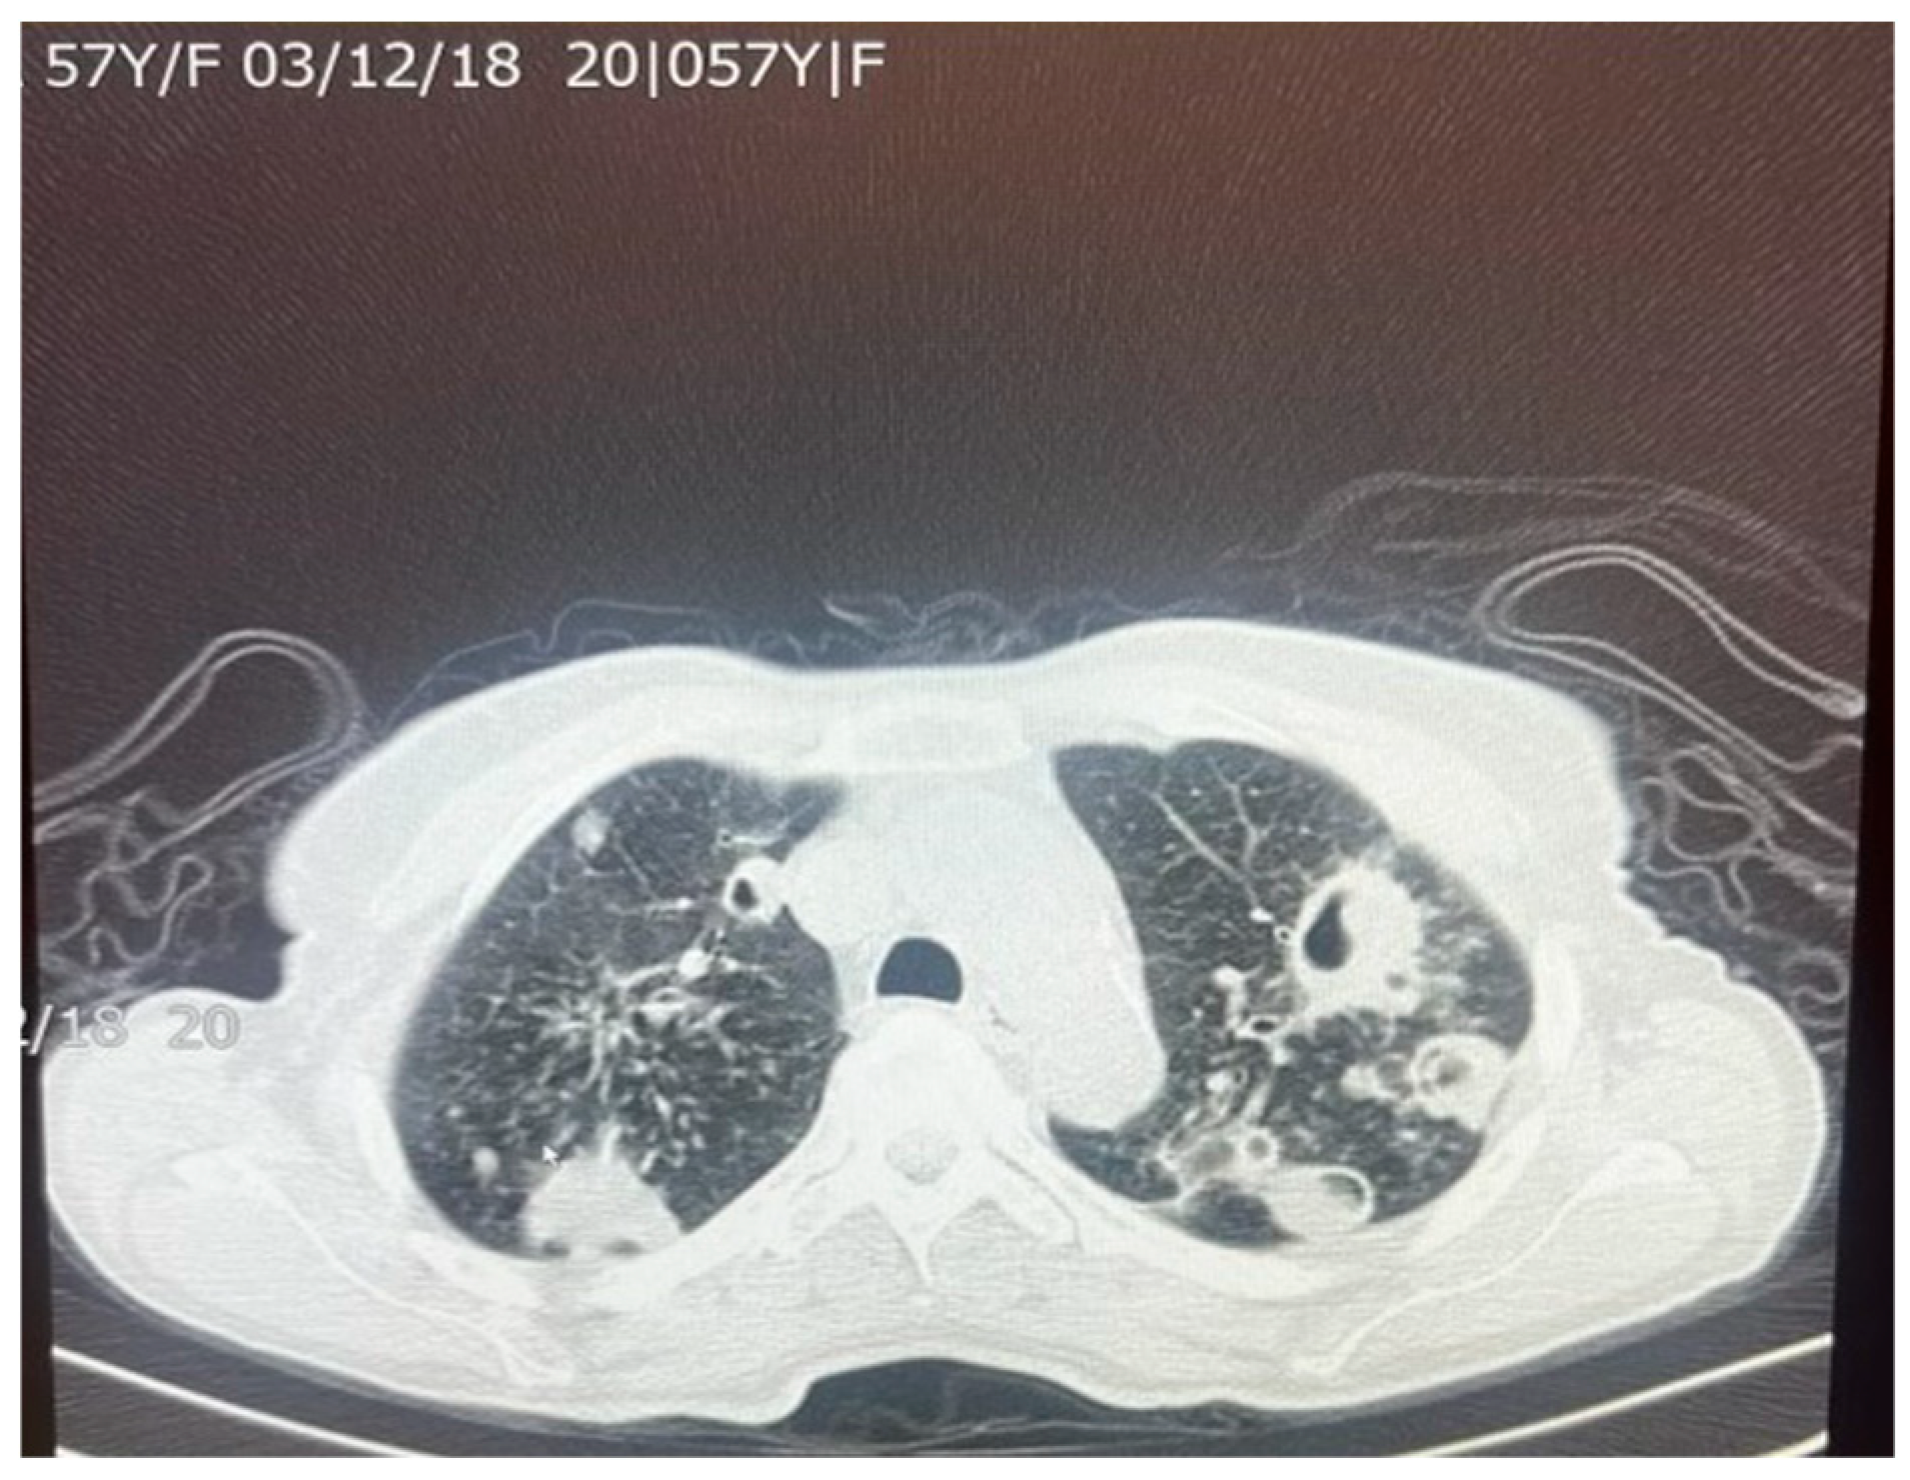

Figure 5. An axial chest CT scan of a 57-year-old female patient with pulmonary TB, showing bilateral pulmonary cavities and multiple nodules. The cavities are seen predominantly in the upper lobes, with irregular thickened walls, suggestive of active TB. The nodular lesions surrounding the cavities represent granulomatous inflammation, which is characteristic of TB infection. These findings are typical of post-primary TB in adults.

M. tuberculosis can alter the normal lung architecture in cases of both latent and active disease and even cause permanent damage after resolution of the infection. Damage to lung tissue, such as the replacement of tissue with scar tissue, can permanently alter respiratory function, leading to significant morbidity well after the bacterium has been cleared. Figure 5 and Figure 6 illustrate the pattern of damage that points to the reactivation of TB. The cyclical process of tissue injury, immune-mediated inflammation, and healing contributes to fibrosis and calcification, which may lead to both obstructive and restrictive patterns of lung disease. Obstructive dysfunction can result from airway inflammation, loss of elastic recoil, and post-infectious bronchiectasis—the latter characterized by permanent dilation of the bronchi. On the other hand, restrictive changes arise from exaggerated immune responses and chronic inflammation, leading to fibrosis and stiffening of the lung parenchyma. The degree of respiratory mechanic abnormalities (i.e., pulmonary function tests) from M. tuberculosis infection can vary depending on multiple factors such as patient age, geographic location, or the drug resistance of the bacteria [25].

M. tuberculosis infection often leads to injury to the pleura. This includes the thickening and fibrosis of the pleura, and in many of these cases, patients further form calcification. About 40.9% of patients with fibrosis form these calcifications, as demonstrated in a CT-based study by Deshpande et al. [9]. The presence of fibrosis often results in decreased lung capacity on one side of the chest. This can be due to the cavities that form within the lungs as a result of the infection. In patients who had a single cavity in their lungs, fibrosis was found 100% of the time and calcification 80% of the time. In addition, 90% of these single cavities were found in the upper lobes of the lungs [9]. Upper lobe damage to the lungs can be seen in Figure 2. Further evidence of the presence of M. tuberculosis can be observed in Figure 3, in which many acid-fast bacilli are shown. The consistent presence of fibrosis and calcification in these cases suggests prolonged infection. This represents the host’s attempt to contain the mycobacterial focus. Fibrosis may contribute to disrupted lung structure and functional impairment of the lung, while calcification often marks the healing or inactive phase of a granulomatous lesion.